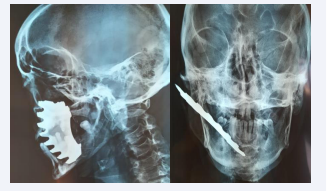

He was taken to the emergency department of Sahloul University Hospital, Sousse, Tunisia. Physical examination, shows a big Fragment of the cut-off wheel protrudes on the right side of the face from the upper cheek to the middle of the chin. The neurological examination was normal and the patient was conscious during the exam. A standard radiographic X-Ray with frontal and profile views was done quickly in the emergency department showed a metallic foriegn body anchroched to the mandible (Figure 1D). The history for the injury conclude to work accident.

X-ray of the face with frontal and profile views revealing a broken  wheel fragments anchored in the bone.

Figure 1D: X-ray of the face with frontal and profile views revealing a broken wheel fragments anchored in the bone.

In our case, a patient with mandibular fracture required nasal intubation for occlusional arrangement. Plain film and A computerized radiography of the face is a basic requirement because radiographs can confirm the location, size, shape, and number of foreign bodies , especially ones made of metal [7]. Free movement of the foreign object is also important if it is firmly anchored in the bone because can cause a massive bleeding. For the reduction of this type of fracture Titanium was preferred than resorbable materials that can cause infection [5,7].